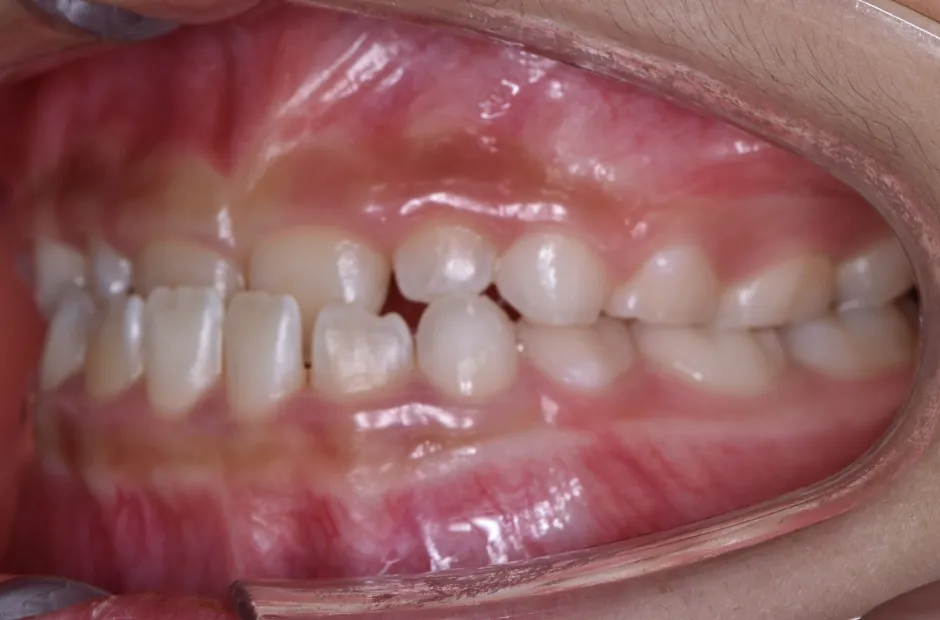

前歯部反対咬合

| 診断名・主訴 | 前歯部反対咬合 |

|---|---|

| 年齢・性別 | 14歳・男性 |

| 治療期間・回数 | 1年2か月 |

| 治療に用いた主な装置 | ブラケット矯正 |

| 抜歯部位 | なし |

| 治療費 | 60万円(税抜) |

| リスク・副作用 | 装置による違和感・疼痛・歯肉退縮・歯根吸収・虫歯のリスクなど |

治療中

治療後